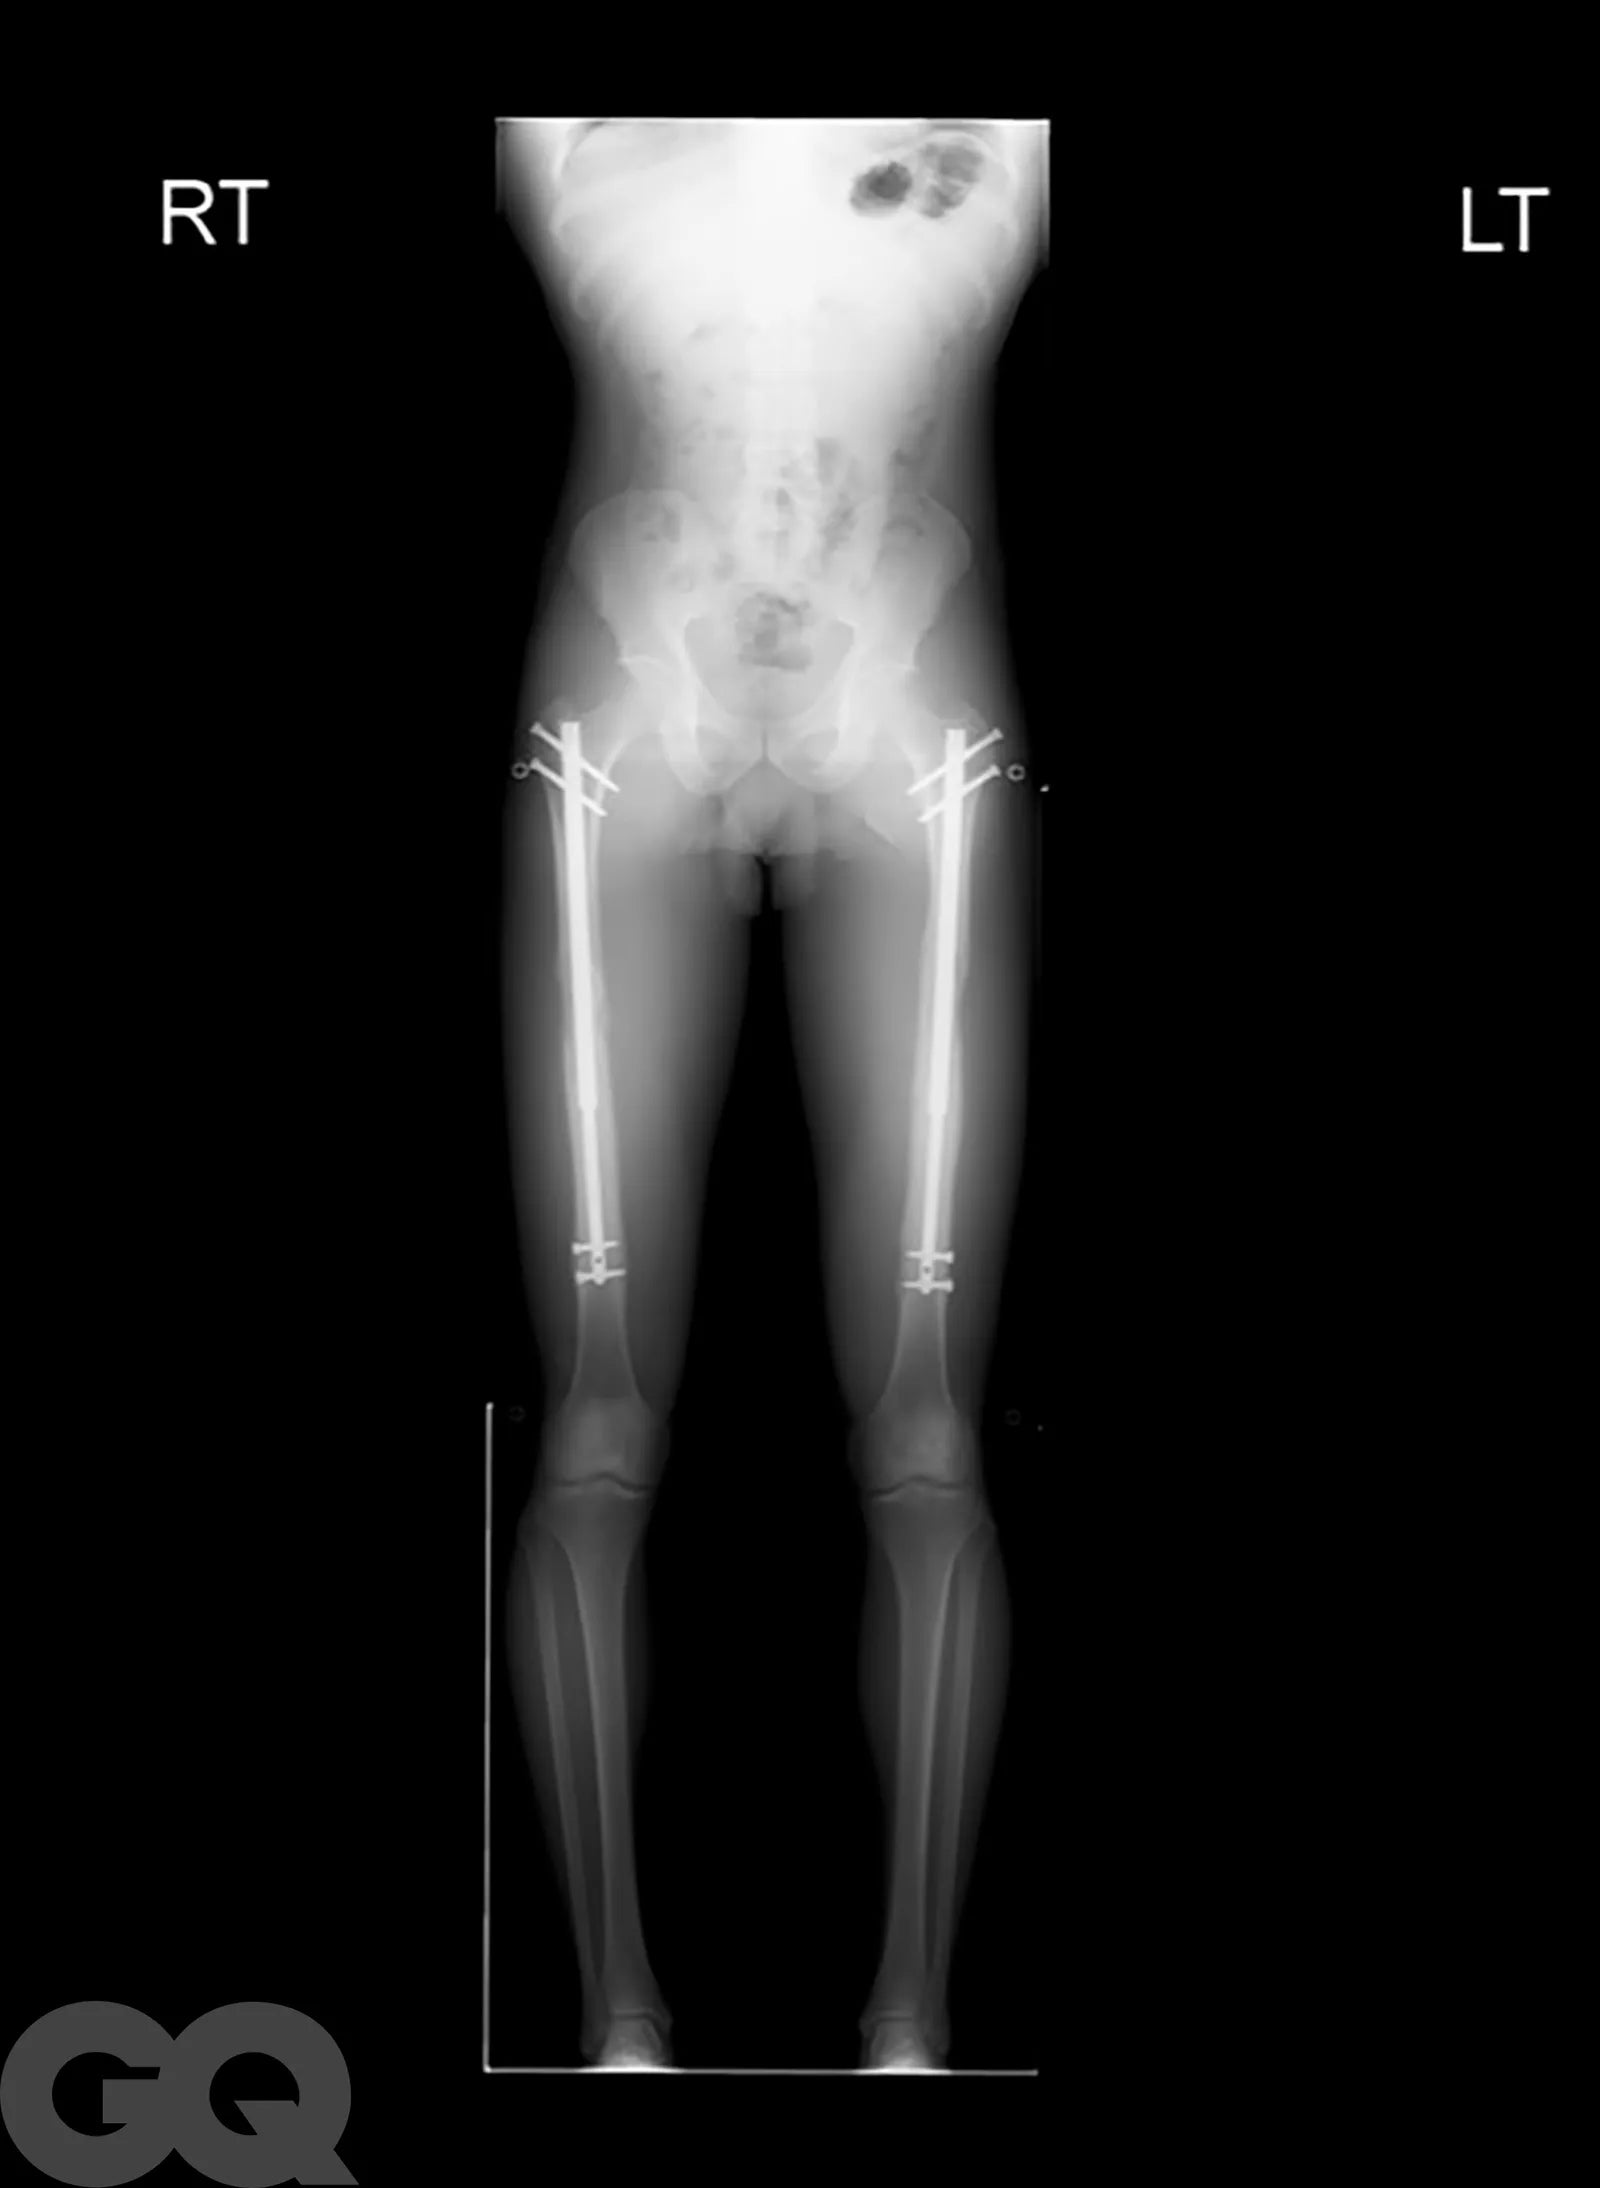

Hundreds Of Short Kings Around The Country Are Flying To Vegas To Have Their Legs Broken And Rods Inserted So That They Can Grow 3-6 Inches

- People are flying out to Vegas for surgeries where they literally have both of their femurs snapped by a chisel-like instrument to grow 3 inches

- The doctor drills a 2-foot long bit straight up through the femur and inserts a rod into the femur

- Some sort of remote-controlled magnet moves the rod one millimeter every day for 90 days so that the bone continues to heal itself into a longer bone (this is tough to word but you get the gist)

- If 3 inches is not enough, you can also circle back and get your tibias snapped and go for 3 more inches for a grand total of 6 inches

- The full healing process for the femurs takes about a year and costs anywhere between $70k and $150k.